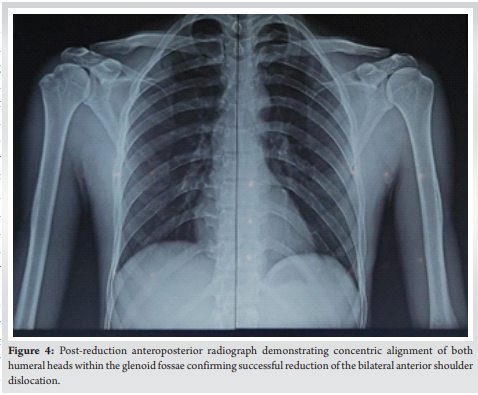

After routine pre‑anesthetic evaluation, the patient underwent closed reduction under intravenous sedation. The Kocher’s maneuver was applied sequentially to both shoulders with successful reduction confirmed clinically and radiographically (Fig. 4).

Immediate post‑reduction X‑rays showed concentric and congruent glenohumeral articulations. Both shoulders were immobilized in slings with internal rotation for 3 weeks. Early pendulum and passive range‑of‑motion exercises were started after immobilization, followed by gradual active physical rehabilitation. Epilepsy was evaluated by a neurologist and treated appropriately.